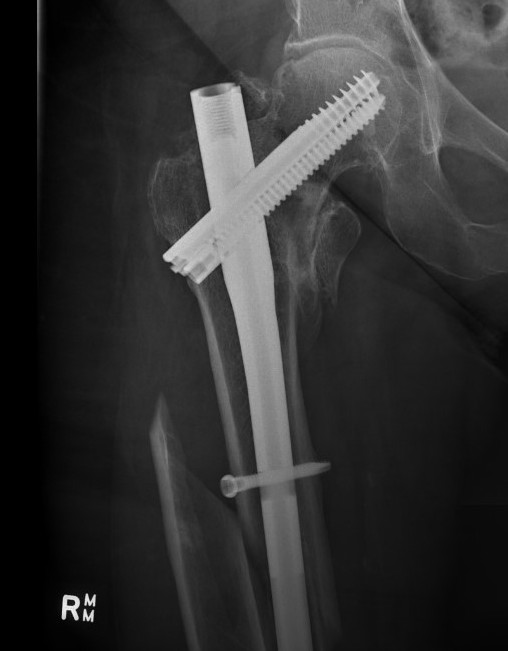

Cephalomdeullary nail

- Short / long

- one screw / two screws / blade

Cephalomedullary nail / Proximal femoral nail

Mechanical advantages

- load sharing rather than load bearing

- decreases lever arm

- supports medial cortex

Surgical advantages

- smaller incision / minimally invasive

- reduced blood loss

- shorter surgical times

Indications

- reverse oblique

- unstable fracture / loss of lateral buttress / loss posteromedial support

- subtrochanteric extension